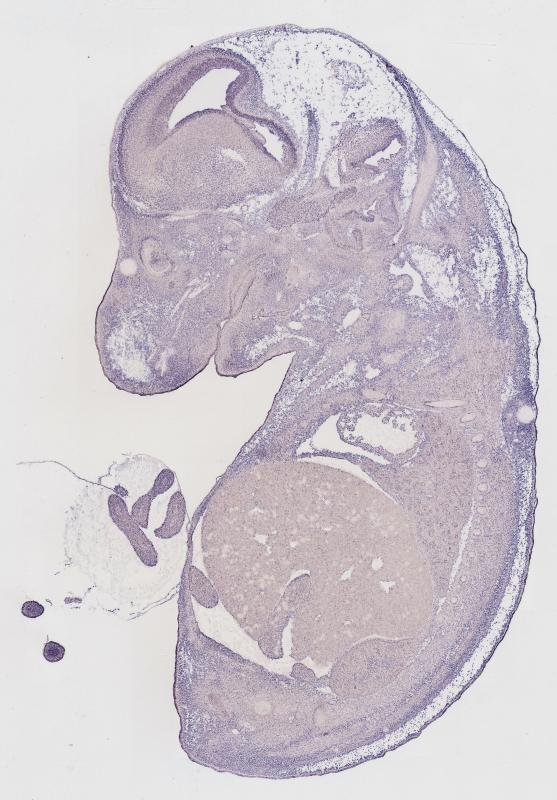

Specimen

MH837; Specimen C1251:

embryonic day 14.5